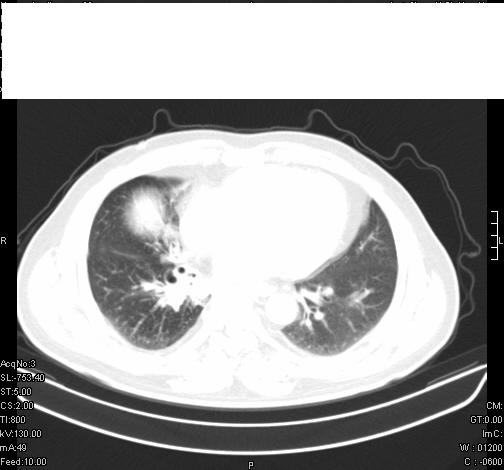

标题: CT6685:右肺阻塞性炎症,增强CT。

前几天,发了患者的平扫片,患者抗炎一周后增强扫描。右中叶病灶吸收明显,但下叶病灶未见明显吸收。右肺门可见结节影,看来凶多吉少

右肺下叶散在的斑片状致密影,下叶支气管变窄。考虑:右肺慢性炎症。

支持:右肺下叶散在的斑片状致密影,下叶支气管变窄。考虑:右肺慢性炎症。

第18幅,好像不能简单用炎症解释,前几天我发平扫时,90%人支持肺癌,现在好像大家更倾向于炎症了,我觉得还是不能排除肺癌。

右肺下叶支气管壁不规则增厚,右肺下叶有斑片状影分布。考虑右肺中央型肺癌伴右肺下叶阻塞性改变。建议支纤镜检查。平扫比增强较好显示了病变情况。

既然抗炎治疗有效,可继续治疗;右肺下叶支气管管腔狭窄,管壁增厚,右下肺见斑片状高密度影,右侧主支气管后见结节影(淋巴结?),肺癌不能排出。